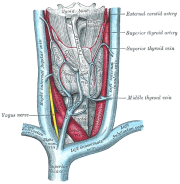

| 06:58, 12 בנובמבר 2012 | בלוטתתריס114.png (קובץ) |  |

231 קילו־בייטים | Motyk | 1 | |